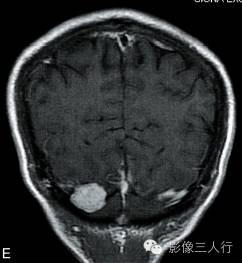

A.T2WI横断面;B.T1WI横断面;C、D、E.增强横断面、矢状面、冠状面;F.HE×100

图A、B:平扫MRI显示右侧小脑后缘类圆形结节状病灶,大小约1.4cm×2.0cm×1.8cm,在T2WI呈稍高信号,T1WI为稍低信号,边界清楚,信号均匀,局部脑组织受压内移。图C~E:Gd-DTPA增强扫描显示结节呈较均匀明显强化,病灶边缘清楚,其中在横轴位图像显示肿瘤中央部分强化较周围明显,且类似日光放射状。矢状位、冠状位图像见肿块强化变均匀一致,紧贴小脑后方硬脑膜或颅骨,但未见明显硬脑膜尾征。